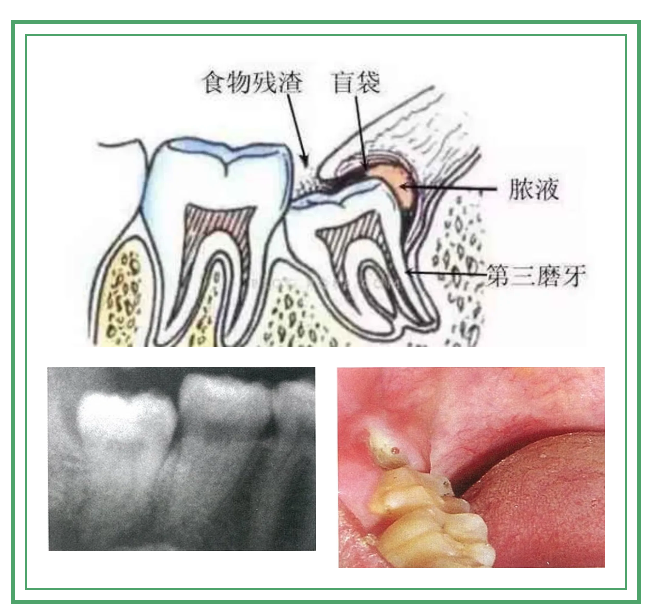

3.反复引起牙龈肿痛的智齿

牙齿的萌出需要过程,当部分牙龈覆盖在牙齿上面时,会形成盲袋,清洁不佳的情况下可因细菌积聚导致牙冠周围牙龈炎(冠周炎),从而出现肿痛。一般在牙齿完全萌出后,不适症状即可消失。如果肿痛反复出现在智齿的位置,那大多是由智齿萌出方向不正导致的。反复的智齿冠周炎轻则只是牙龈肿痛,重则可引起头颈部组织间隙细菌感染。